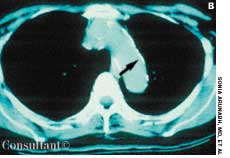

A 33-year-old man with AIDS presented to the emergency department with fever, dyspnea, cough, and pleuritic chest pain of 3 days’ duration. He had had a Pneumocystis carinii infection 3 years before recently emigrating from the Dominican Republic to the United States.